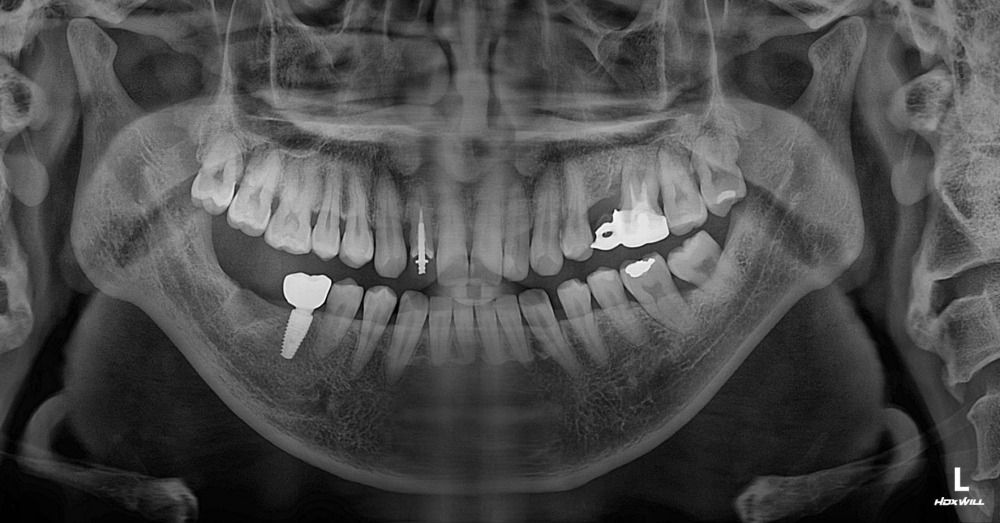

รากฟันเทียม Straumannนี่ครับ... ตำแหน่งฟันที่มีปัญหา ฟันกรามซี่กลางล้ม คุณหมอบอน วินิฉัย แล้วให้แนวทางการรักษาตามนี้ครับ

VP Dental Clinic

- ถอนฟัน 1 ซี่ ที่เอียง

ถ้าปล่อยไว้ก็จะล้มไปเรื่อยๆ แล้วจะทำให้บดเคี้ยวอาหารไม่สะดวกมากยิ่งขึ้น

- ติดตั้ง รากฟันเทียม สตรอแมน 1 ซี่ ( Straumann )

ทำรากฟันเทียม ที่ไหนดีภาพ X-ray ช่องปาก ลุงเด้ง หลังจากที่ทำรากฟันเทียม เสร็จสมบูรณ์แล้ว